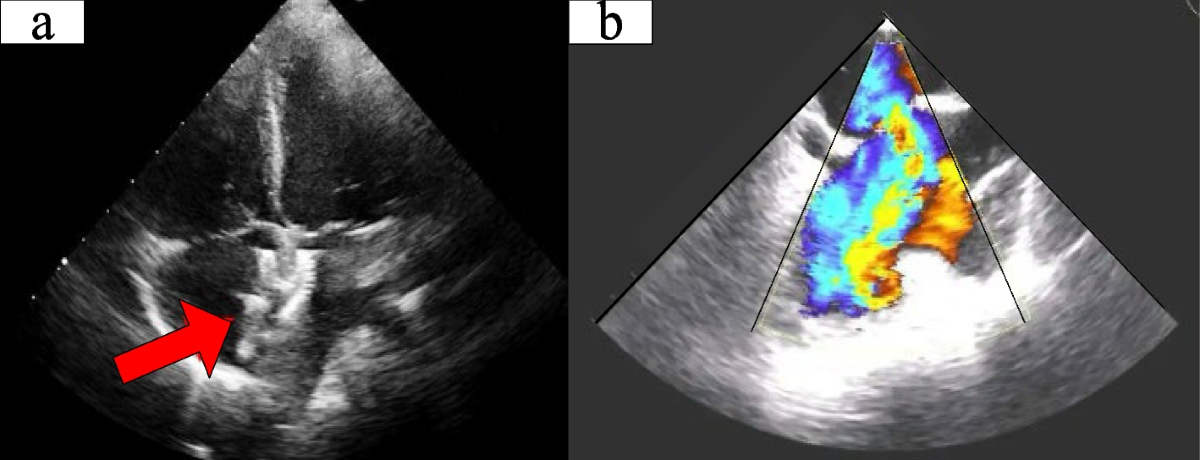

- Siêu âm tim: Đây là phương pháp chẩn đoán hình ảnh quan trọng giúp xác định chính xác loại bệnh tim bẩm sinh, mức độ nghiêm trọng và hướng điều trị phù hợp.